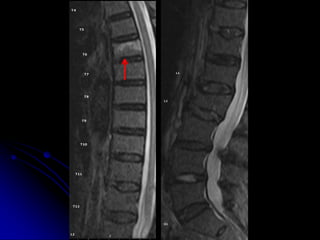

T6 T6

L2